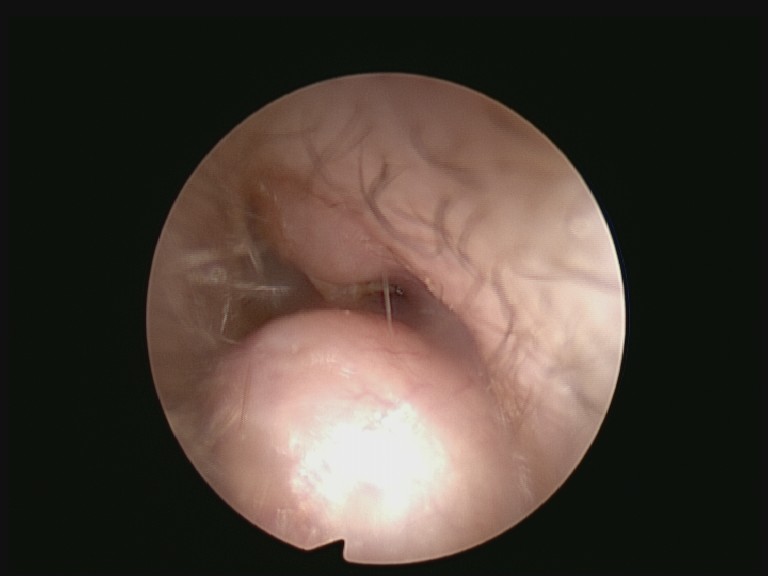

Photo of a surfer’s right ear showing significant narrowing caused by new bone growth (exostosis). They had been suffering from recurrent ear infections in this ear. A year previously they had their left ear exostosis successfully removed.

These bone growths aren’t dangerous and most people who have Surfer’s Ear (exostosis) are completely symptom free. They may remain symptom free too. This is because a lot of people reduce the amount of time they spend in the sea before problem’s start. Getting a job or having children can be useful for that.

Some surfers who develop exostosis aren’t so lucky. They are plagued by constant pain, recurrent infections and rarely in some of the worst cases suffer with a constant ringing in their ear. Surfing to them, once perhaps irreplaceable as a pastime, now rapidly becoming something relegated to their past.